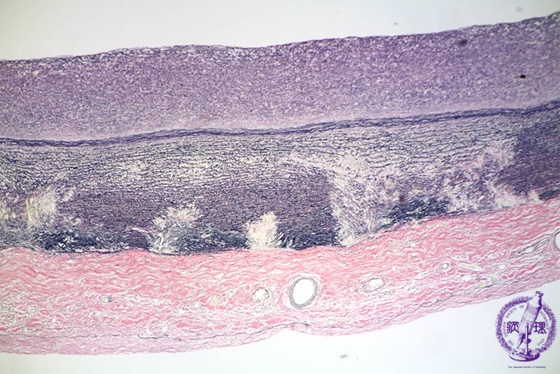

- (13)Takayasu arteritis

Microscopic image (EVG stain, low power view): There is disruption of the elastic lamellae in the outer layer of the media (within the circle).